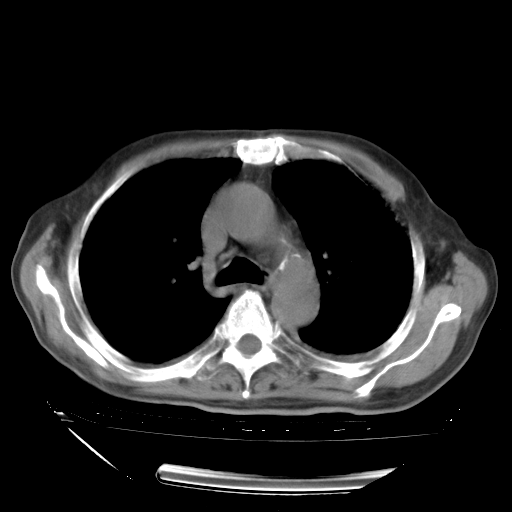

甲强龙80mg/日+抗结核治疗(异烟肼+利福霉素+乙胺丁醇)10天。复查肺部CT。

治疗10天肺部CT

94186 3 10.bmp

94186 3 11.bmp

94186 3 12.bmp

94186 3 13.bmp

94186 3 14.bmp

94186 3 15.bmp

94186 3 16.bmp

94186 3 17.bmp

94186 3 18.bmp

94186 3 19.bmp